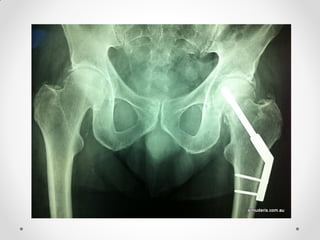

Film pelvis AP

Film Rt.Hip lateral

Film Rt.knee AP-lateral

Film CXR

Closed fracture Rt.femoral neck

Plain radiograph

• Shenton’s line disruption (continuous line from medial edge of

femoral neck and inferior edge of the superior pubic ramus)

• lesser trochanter is more prominent due to external rotation

of femur

• femur often positioned in flexion and external rotation (due to

unopposed iliopsoas)

• asymmetry of lateral femoral neck/head

• sclerosis in fracture plane

• smudgy sclerosis from impaction

• bone trabeculae angulated

• nondisplaced fractures may be subtle on x-ray